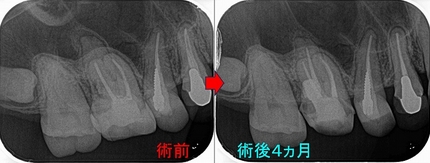

歯からくる副鼻腔炎で抜歯!?

患者さんは50代女性

2ヵ月前に歯茎が腫れその後フィステルが出てきた。

副鼻腔炎の症状もあり、近医では抜歯した方がいいと言われた。

現在、副鼻腔の方も詰まり変な臭いを感じる、歯は咬むと鈍痛、寝不足の際に違和感を感じる。

2026 EEdental ATI (1).jpg

近心頬側根に大きな根尖病変が見られます。

患者さんには歯の中の細菌感染が原因になっている可能性が高いので

まずは根管治療を行い⇒様子見 治らなければ外科的歯内療法を行い歯を残しましょうと説明

2026 EEdental ATI (2).jpg

4根 ガッタパーチャーを使用

2026 EEdental ATI (3).jpg

レントゲンでは根尖病変は小さくなってきているように見えます。

術後 1年3ヵ月

2026 EEdental ATI (4).jpg

レントゲンでは病変の大きさは半分ぐらいになってきています。

先日、仮歯が割れてしまったとのことで、本歯を作らせてもらいました。

2026 EEdental ATI (5).jpg

クラウンSet後、根尖病変は殆ど無くなっています。

今回のケース結果的に、歯科と耳鼻科の複合要素でした。

ただ、個人的には発生の原因は歯だったのではないかなと思います。

細菌感染に配慮しない根管治療(神経の治療)を受けると2本に1本は膿んできてしまい、

奥歯だと副鼻腔に炎症が移行して鼻まで問題を起こすことがあります。

なるべく根管治療は細菌感染に対する配慮をしながら治療を受けられた方がいいと思います。